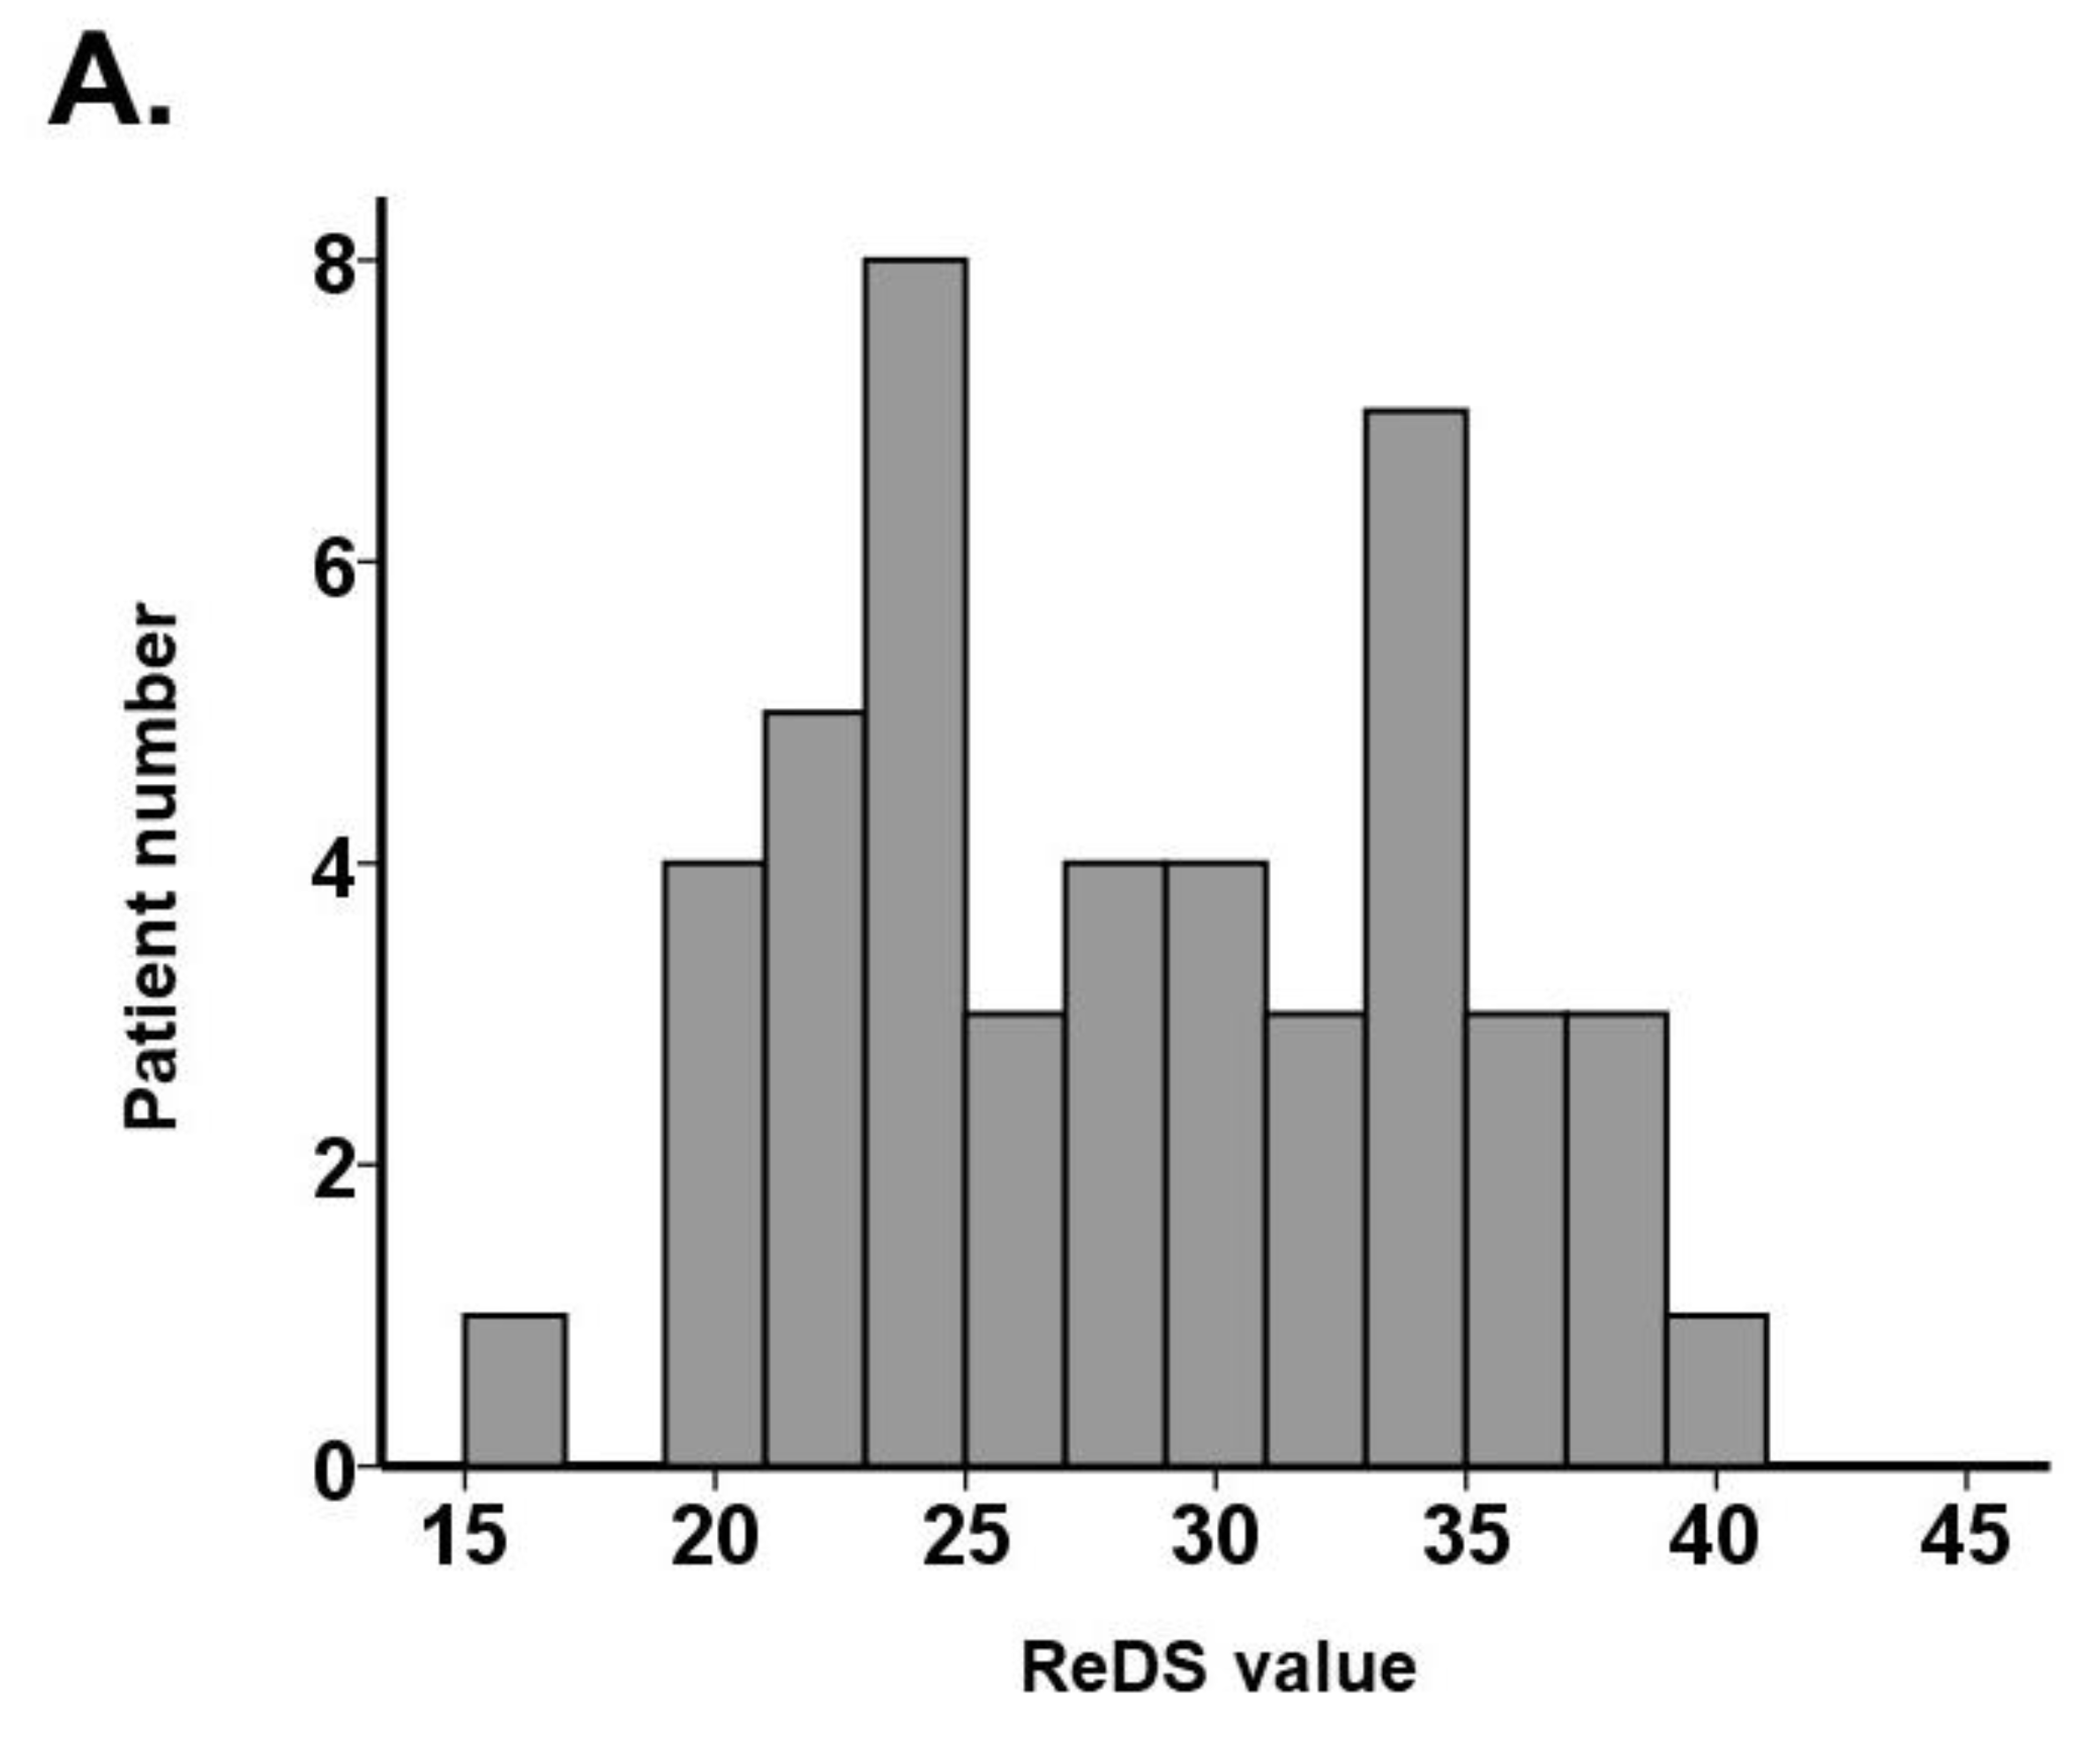

3.2. ReDS Value and %High Attenuation Area